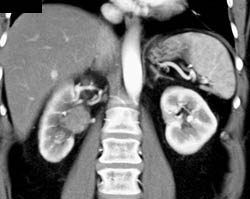

Transitional Cell Carcinoma Right Renal Pelvis in Multiple Phases